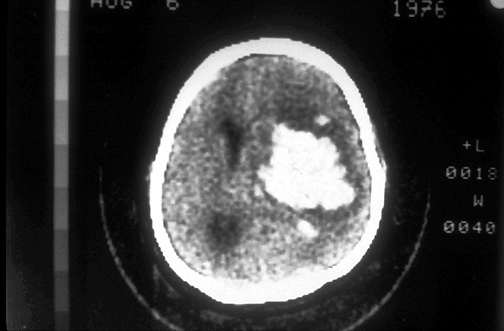

Click on the intracerebral hemorrhage in the CT scan above:

This computed tomographic (CT) scan of the head in transverse view demonstrates an area of hemorrhage arising in the basal ganglia on the left in a patient with a history of hypertension.